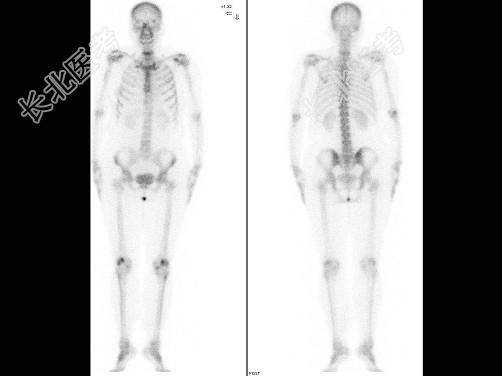

- [材料题] 患者48岁,右乳癌术后7年,感颈部疼痛2个月,行[~99.gif][~m.gif]Tc-MDP骨显像

- 简答题6、患者可能的诊断是